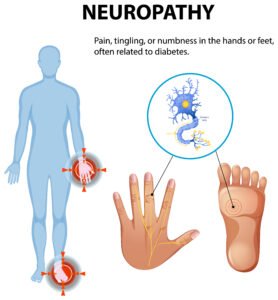

- Neuropathy and Myopathy